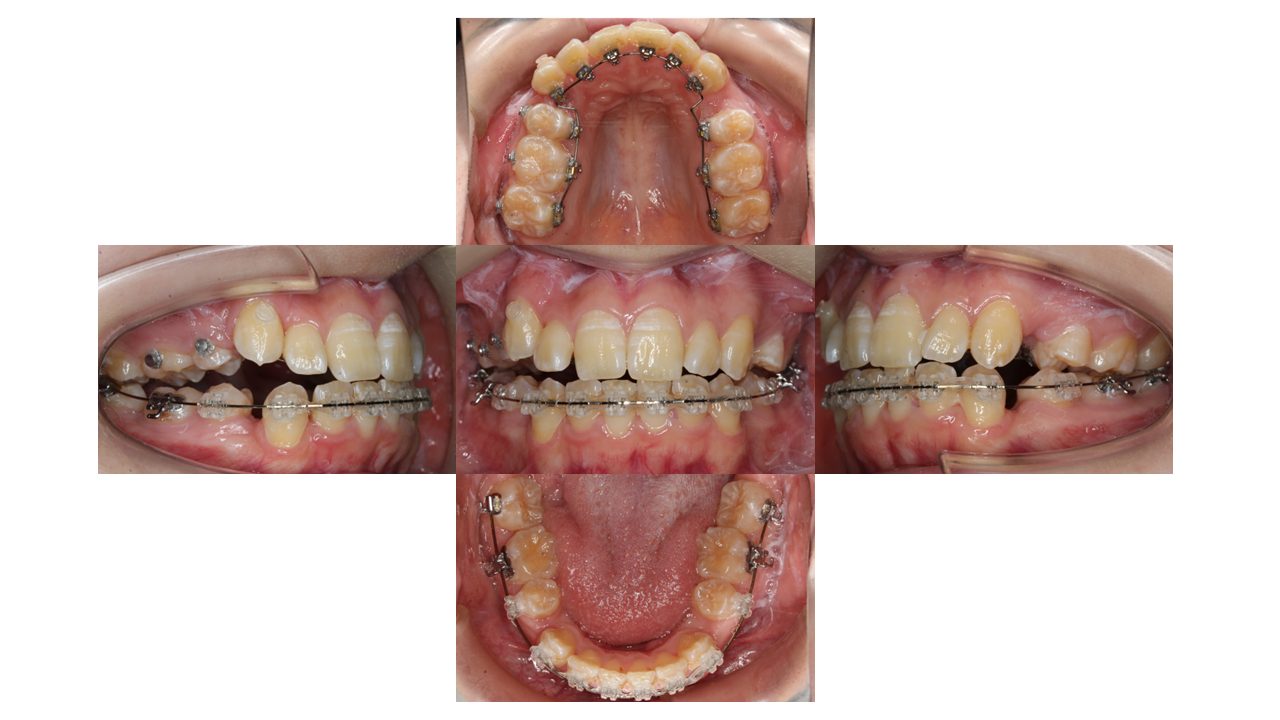

4カ月経過の口腔内の状態です。

徐々に凸凹が改善してきました。